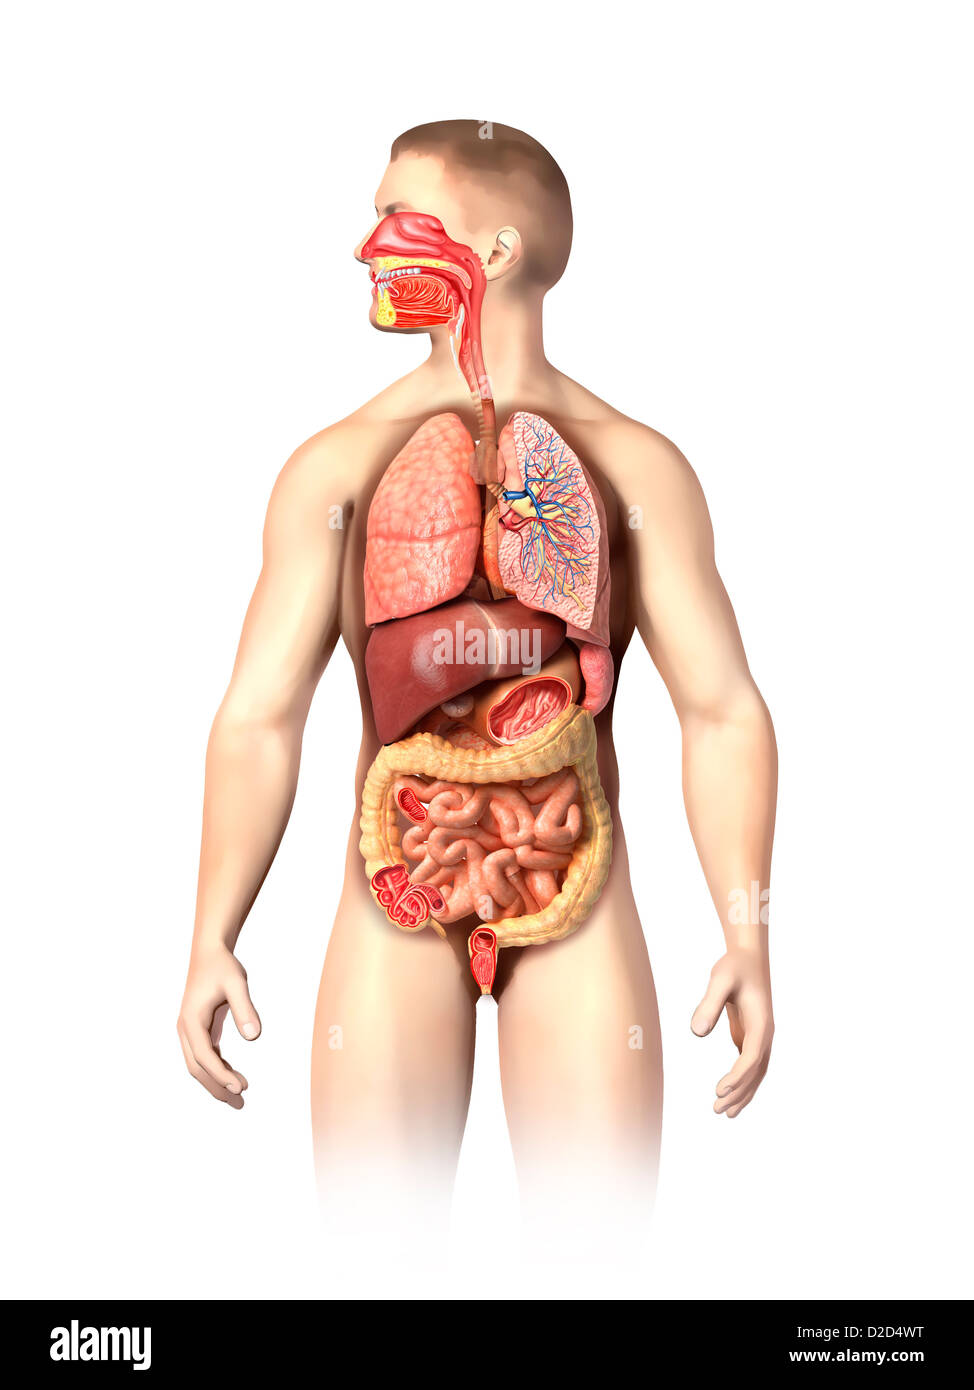

RFDGYRD7–Männliche Anatomie, inneren Organe allein, volle Atmungs- und Verdauungssystem, mit einigen Organen Cutaway. Anatomie-Bild.